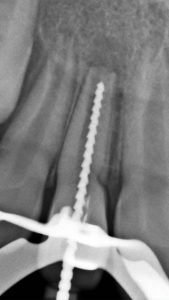

El sistema radiográfico digital New IDA cuenta con un sensor que usa las tecnologías asociadas del CMOS (Complementary Metal-Oxide-Semiconductor), fibra óptica protectora y centelleada. Ese sensor fue fabricado para adquirir la imagen de rayos x digital de alta calidad de la arcada humana y sus estructuras.El proceso de adquisición es realizada posicionado el sensor en la parte interna de la boca atrás de la estructura que se desea realizar el examen.

La estructura debe ser expuesta a una dosis de rayos x usando una fuente externa. Una vez expuesto, el sensor realiza una conversión de los fotones de rayos x en una señal digital y enseguida transfiere para una computadora vía conexión USB (Universal Serial Bus). El software de gestión de imagen dental realiza el interfaz con el sistema New IDA y el usuario, podrá visualizar, mejorar, almacenar, enviar, imprimir entre otras funciones

Es el sensor digital intraoral de DabiAtlante que ofrece imágenes de solución eficiente para obtener un diagnóstico más claro, preciso y avanzado.

Captura imágenes de alta definición en tiempo real.